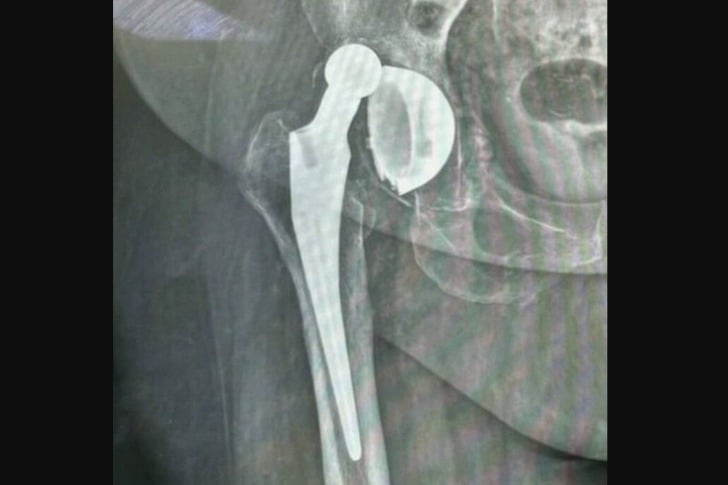

#21 Dieser „Ball“ soll IM Hüftgelenk sein.

Dies kann nach einer Hüftprothese passieren, wenn Sie die Anweisungen, das Bein hochzulagern und das Gelenk für eine bestimmte Zeit nicht zu überdehnen, nicht befolgen. Es kann auch später infolge eines Sturzes auftreten.